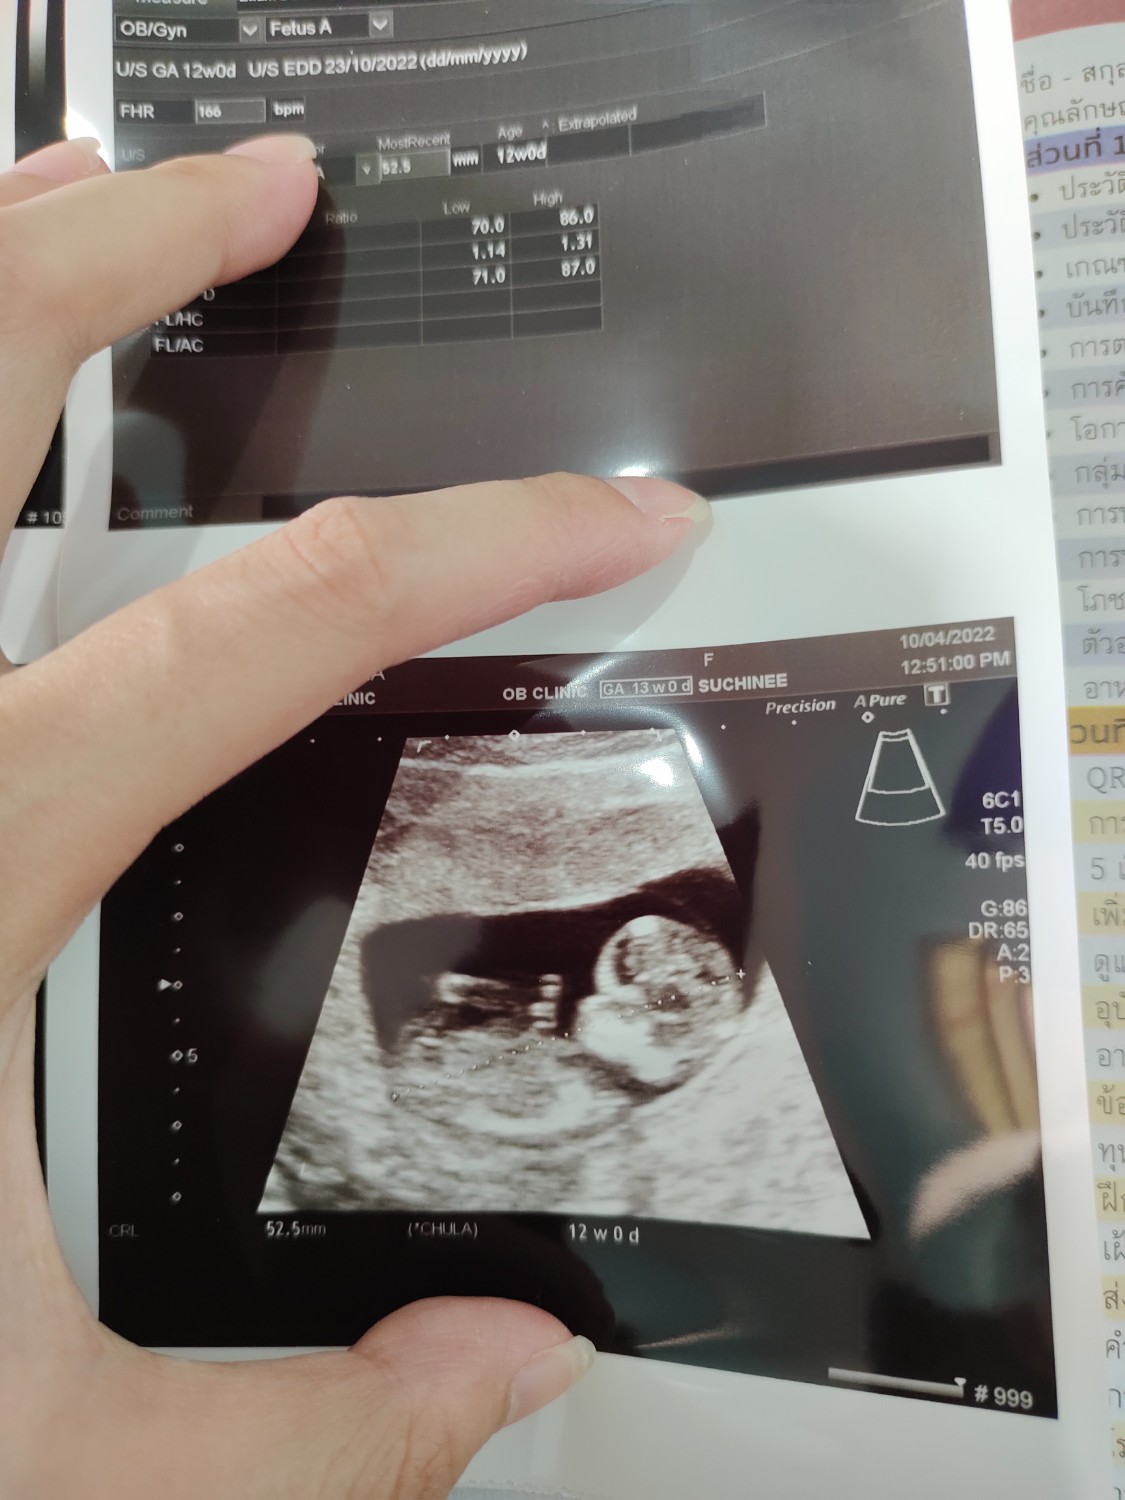

ผลอัลตร้าซาวด์น้องผิดปกติไหมคะ

เราตั้งครรภ์ได้ 12 สัปดาห์ค่ะ ไปอัลตร้าซาวด์ดูน้องมาน้องยาว 5 เซนค่ะ แต่ที่เรากังวลใจ ดูจากในภาพแล้วสังเกตุเองว่าศีรษะน้องแลดูขนาดใหญ่เกินไปไหมคะหรือเราคิดมากกังวลไปเอง รบกวนช่วยชี้แนะด้วยนะคะ